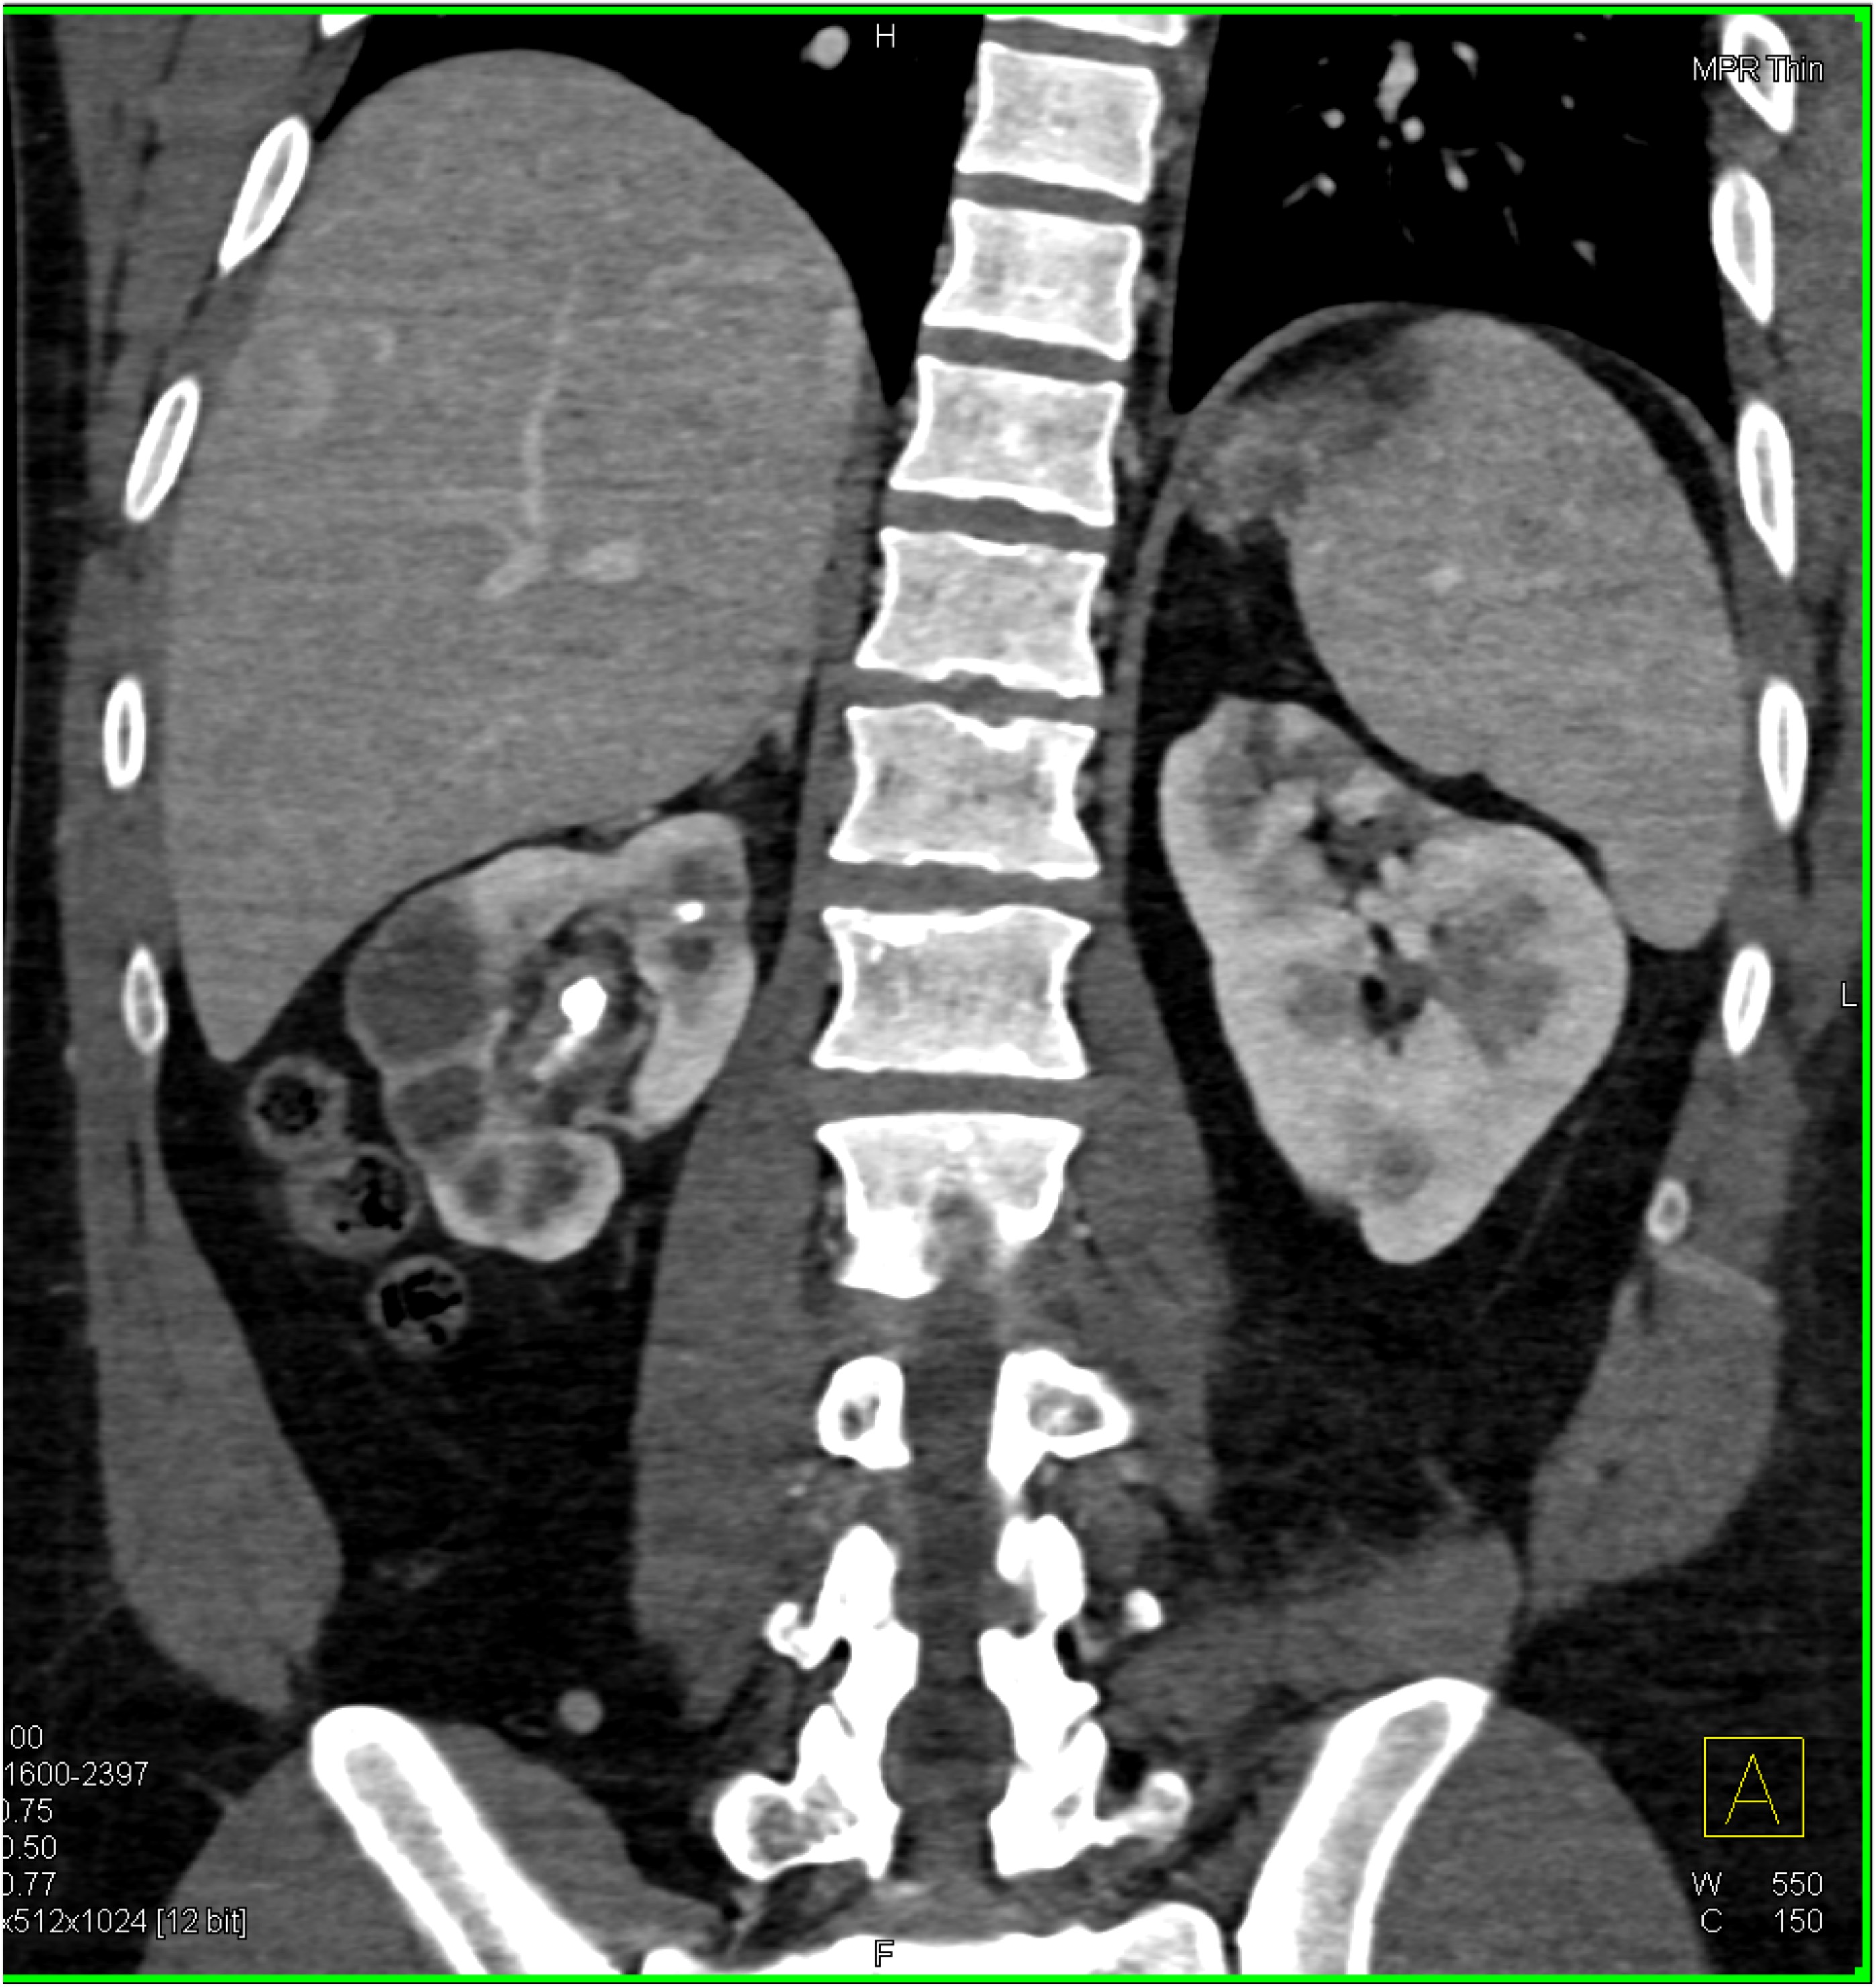

6) The most likely diagnosis in this case is?

lymphoma

acute pyelonephritis

XGP (xanthogranulomatous pyelonephritis)

TB